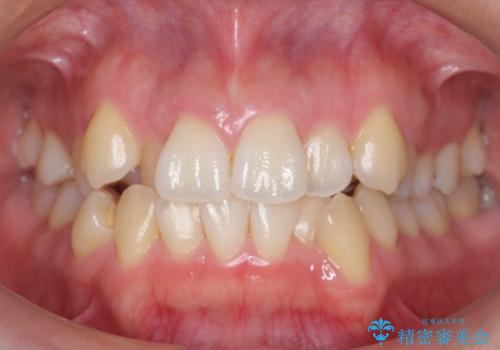

- 20代女性

- 矯正装置

- 審美装置

- 前歯のがたつきと正中のずれを主訴に来院。

小臼歯を4本抜歯しています。